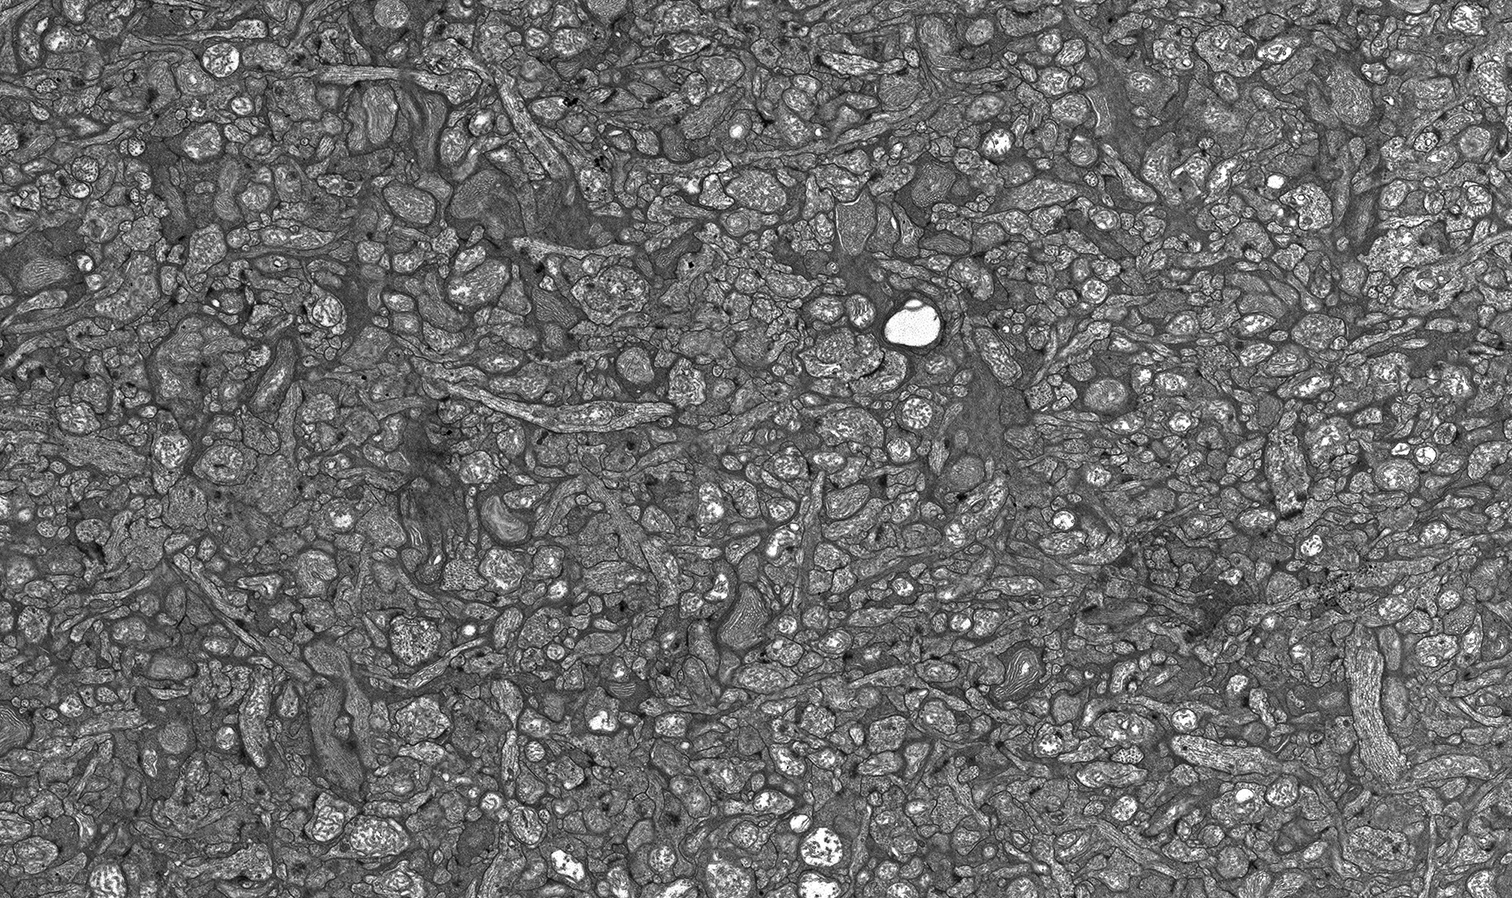

Retinal Complexity